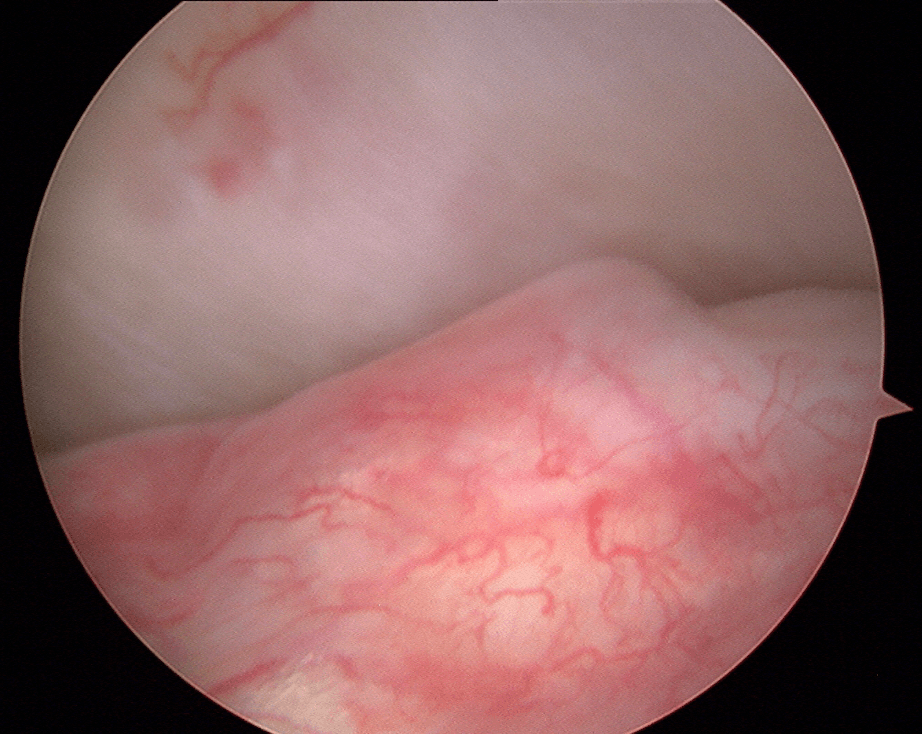

However, some TMDs may require a surgical approach due to their nature or the significant impact they have on function. As a general rule, the surgeon tends to choose the minimally invasive approach that is most appropriate in the circumstances. This may involve a simple joint injection, camera surgery (arthroscopy; an approach that allows access and manipulation of the joint contents without having to open it), or in some cases, open surgery (arthrotomy). Drs. Poirier and Badri have expertise in these fields of practice through their experience and specialization.

Arthroscopic Surgery